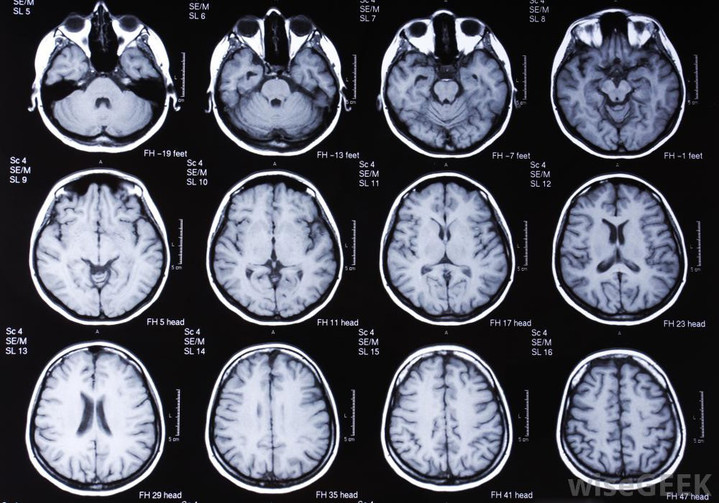

Когда речь заходит о высокоточной и безопасной визуализации структур черепной коробки, магнитно-резонансная томография является методом выбора для врачей различных специальностей. Если вы ищете, где сделать качественное мрт головного мозга в Москве, то одним из проверенных вариантов является клиника «Семейный доктор», где современное оборудование сочетается с высоким профессионализмом диагностов. Это исследование позволяет заглянуть «внутрь» мозга без вмешательства, получив детальнейшие послойные изображения его тканей, сосудов и нервных путей.

Магнитно-резонансная томография — это неинвазивный метод диагностики, основанный на явлении ядерного магнитного резонанса. В отличие от рентгена или КТ, МРТ не использует ионизирующее излучение, что делает ее значительно безопаснее. Томограф создает мощное магнитное поле, под воздействием которого атомы водорода в тканях тела выстраиваются определенным образом. Регистрируя их ответные сигналы, компьютер строит четкие трехмерные изображения. Данное исследование назначают для:

Возможности метода огромны. Он визуализирует малейшие изменения в структуре мозгового вещества, белого и серого вещества, мозжечка, ствола мозга. Врач может обнаружить аномалии развития, очаги воспаления (энцефалит, менингит), аневризмы и мальформации сосудов, признаки нейродегенеративных процессов (болезнь Альцгеймера). Особенно ценна МРТ для онкологии — она не только показывает локализацию и размер новообразования, но и помогает дифференцировать его характер, оценить вовлеченность окружающих структур.